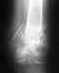

Добрый день!11 сентября мне вставили штифт надувной Fixion после перелома левого бедра (6 сентября). На данный момент по словам врачей сращение идет нормально (тьфу-тьфу), начинаю ходить с одним костылем, нога сгибается в колене полностью. Вот у меня появился вопрос, можно ли ездить за рулем автомобиля в моем случае? Больная нога левая, ей придется нажимать на сцепление (оно довольно мягкое).

Такие нагрузки, как при нажатии на педаль, вполне допустимы на следующий день после операции, не говоря уж о двухсполовиноймесячном сроке, когда уже пора ходить с полной нагрузкой.